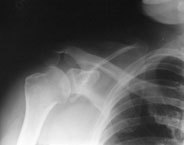

Ein 44-jähriger Patient ist auf dem ersten Eis des Winters ausgerutscht und auf die rechte Schulter gestürzt.

Er klagt über starke Schmerzen im Bereich der rechten Schulter und ein Instabilitätsgefühl im Gelenk. Die Beweglichkeit des Arms ist aufgrund der Schmerzen eingeschränkt, Durchlutung und Sensibilität sind normal.

linke Schulter pa

Welche Befunde liegen vor (mehrere richtige Antworten möglich)?